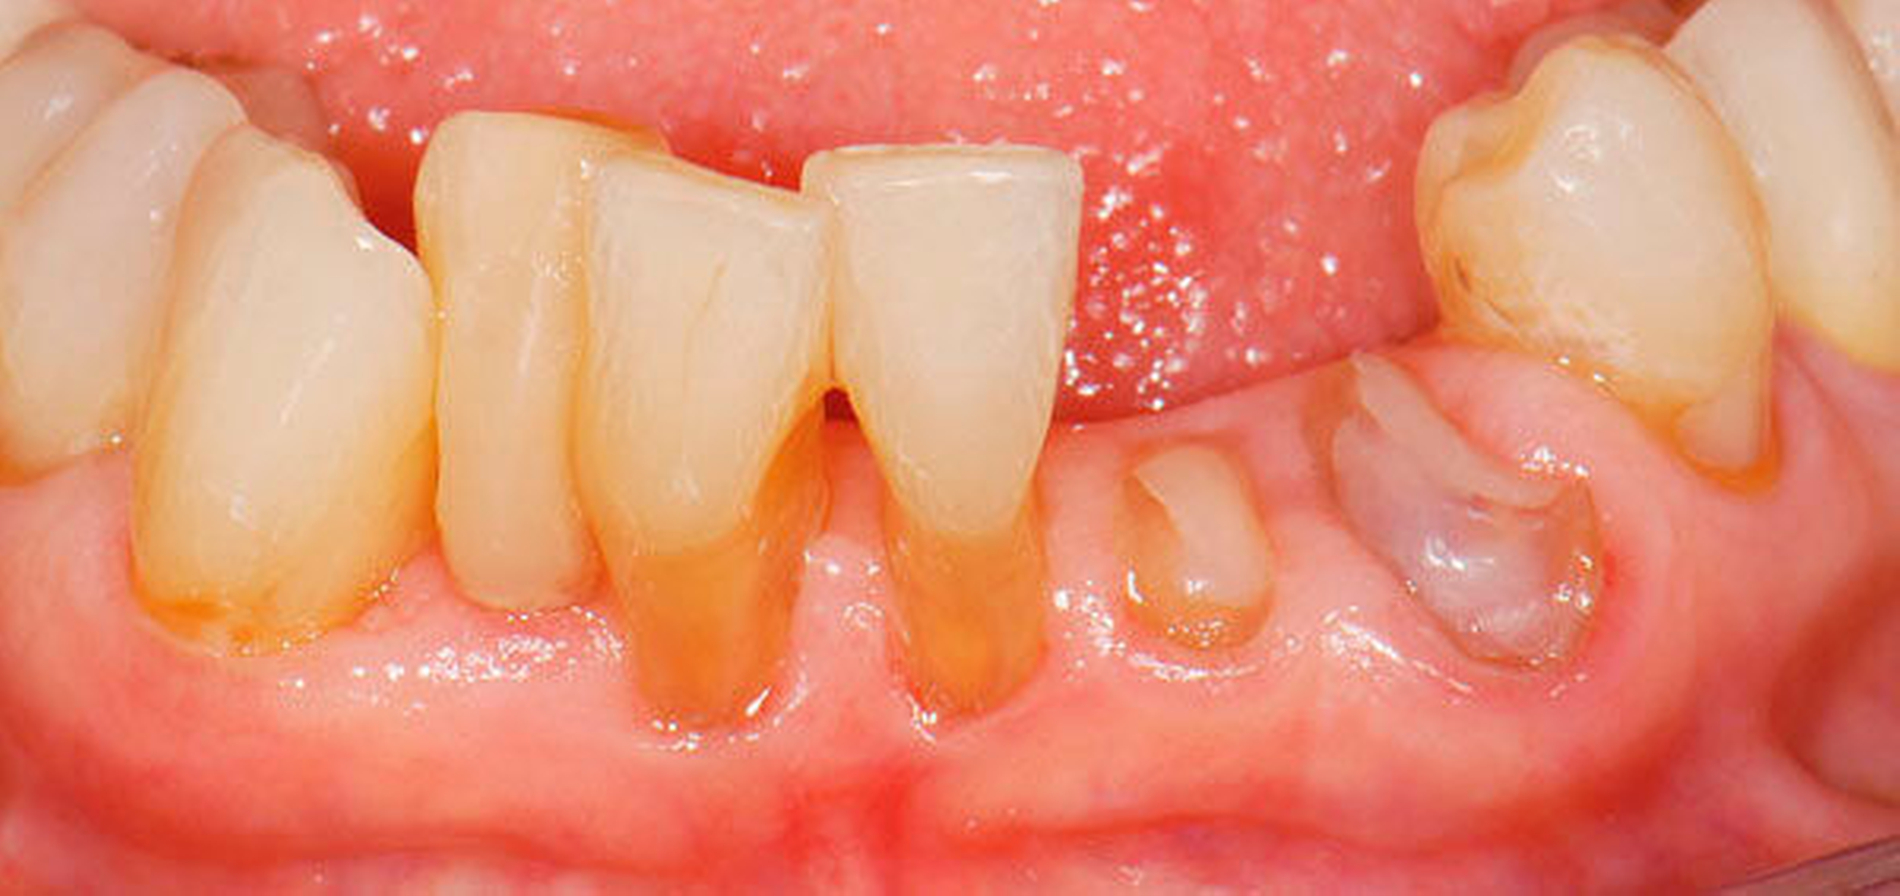

4. Vorgehen bei frakturierten Zahnkronen/Wurzelresten

Üblicherweise werden frakturierte Zahnkronen beziehungsweise Wurzelreste restaurativ wieder aufgebaut oder es erfolgt eine Extraktion. Im Seniorenalter erscheint es hingegen manchmal als Kompromissmaßnahme vertretbar, Wurzelreste vorerst zu belassen und etwa mit adhäsiv eingebrachtem Komposit knapp über Gingivahöhe abzudecken. Dies bietet sich vor allem dann an, wenn die Wurzelkanäle bereits obliteriert und endodontische Interventionen nicht erforderlich sind (Tabelle 4) [Staehle et al., 2017].

Abbildung 4: Anliegen eines 76,5-jährigen Patienten (Anfrage per E-Mail). Zitat: „Mich plagt eine … Entzündung des Mundraums, die auch das Zahnfleisch meiner Zahnstummel angreift, weshalb ich nur noch Breiartiges zu essen vermag. Ein Angsthase wie ich geht zum Zahnarzt NUR unter dem Eindruck akuter Schmerzen!“

Damit wird die Hygienefähigkeit zumindest partiell verbessert und Spielraum für künftige Planungen und Vorgehensweisen unter besseren Bedingungen belassen. Das Procedere ist in den Abbildungen 4 und 5 beschrieben. Bei dem in Abbildung 4 vorgestellten Patienten lag eine Oralphobie im Seniorenalter vor. Die Verlaufsbeschreibung macht deutlich, dass selbst im fortgeschrittenen Alter eine Adaptation an zahnärztliche Interventionen im Einzelfall noch möglich ist.